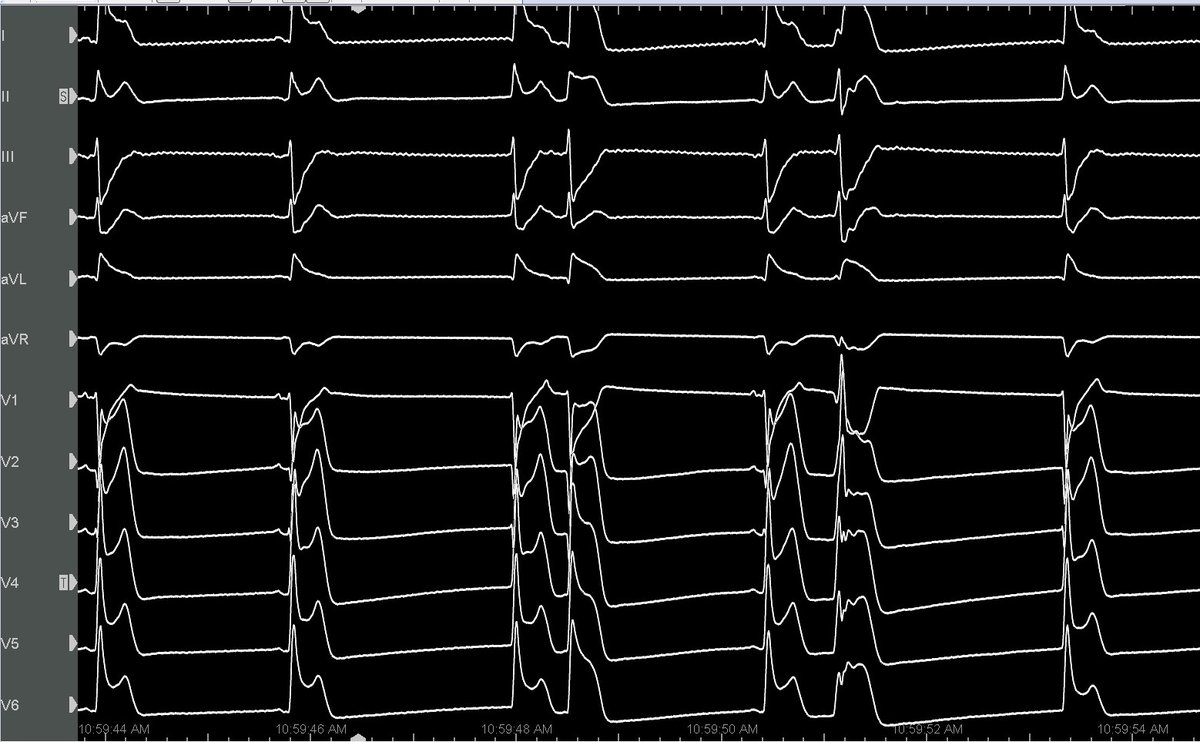

Ethanol VT ablation a challenging case from our lab Refrerered for Recured VT after ablations, 1st anteroseptal VT Optrell, revealing a complete intramural circuit. Ethanol infusion → terminated the first VT. 2nd inferoseptal: Ethanol into MCV septal branch terminated VT

Our Ethanol Ablation for VT series! Non-ischemic CMP No endo scar, septal reentry w/ focal endo-epi activation 💡 Intramural circuit suspected ⛔️ Long endo RF → transient VT stop 🎯 Best precocity at AIV septal branch os endo neighbor Ethanol injection VT termination #Epeeps